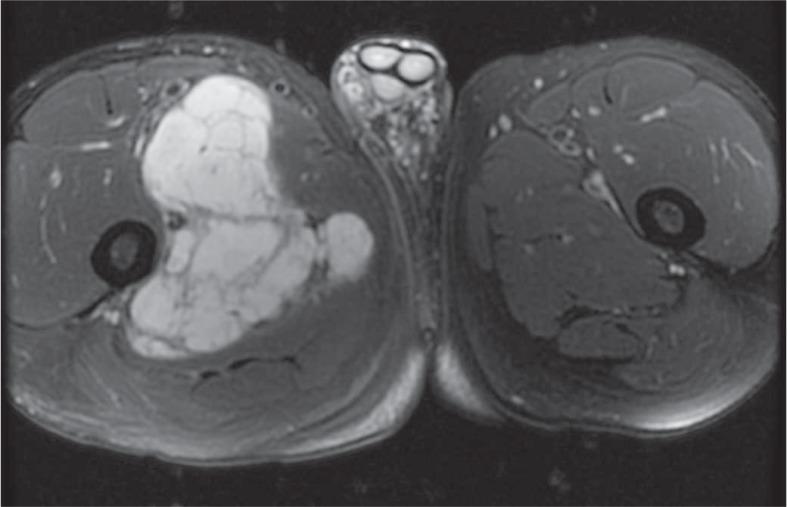

Among 13 patients, 3 died during the timeframe of this study. Nine patients had primary tumor in the lower extremity, and average tumor size was 9.3 cm (range 3.3-18 cm). On MRI, primary tumors were hyperintense on T2, isointense to muscle on T1, and demonstrated peripheral/septal enhancement. Three patients had local recurrence and 12 had metastatic disease, with lung involvement being the most common. Tumor density on contrast enhanced CT ranged from 8.2 to 82.9 Hounsfield unit (HU). FDG-PET/CT imaging was performed in 3 patients. One patient had no FDG avid disease and 2 patients had metastatic disease with standard uptake values (SUV) of 2.8 and 7.4. The patient with intense FDG uptake demonstrated more solid appearing tumor burden and had the shortest survival.

在 13 例患者中,有 3 例在本研究期间死亡。9 例患者的原发肿瘤位于下肢,平均肿瘤大小为 9.3cm(3.3-18cm)。在 MRI 上,原发肿瘤在 T2 上呈高信号,在 T1 上与肌肉等信号,呈外周/间隔增强。3 例患者有局部复发,12 例有转移,其中肺部受累最常见。增强 CT 上肿瘤密度范围为 8.2-82.9HU。3 例患者行 FDG-PET/CT 检查。1 例患者无 FDG 摄取,2 例患者有转移,标准摄取值(SUV)分别为 2.8 和 7.4。FDG 摄取量高的患者肿瘤负荷更呈实性外观,生存时间最短。